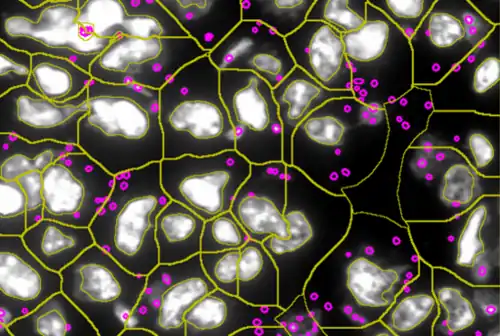

In this process, a tissue sample, either formalin-fixed paraffin-embedded (FFPE) or frozen tissue section, also referred to as “cryocut”, is labelled with either immunohistochemistry[3](IHC) or immunofluorescent markers, scanned with high-throughput slide scanners and the data gathered from virtual slides is processed and analyzed using software that is able to identify individual cells in tissue context automatically and distinguish between nucleus and cytoplasm for each cell.[1] Additional algorithms can identify cellular membranes, subcellular structures (like cytoskeletal fibers, vacuoles, nucleoli) and/or multicellular tissue structures (glands, glomeruli, epidermis, or tumor foci).[4]Fluorescence Activated Cell Sorting (FACS) is a method of analysis that measures fluorescence signals on single cells, where the signal comes from antibody-mediated staining techniques and phenotypes detected by flow cytometry.[5] The major limitation of flow cytometry is that it can only be applied – as the name suggest – to cells in solution. Although methods of “solubilizing” solid tissue exist, any such processing irrevocably destroys the tissue architecture and any spatial context. Hence, tissue cytometry complements the use of flow cytometry and fluorescence microscope[6] in basic research, clinical practice, and clinical trials by providing FACS-like analyses on solid tissue sections (as well as adherent cell cultures) in situ. The advantage of tissue cytometry against flow cytometry is that tissue cytometry does not require the cells to be suspended in fluid, aiding in maintaining the integrity of the tissue structure, morphology, and contextual information, further assisting in precise and accurate contextual analysis that are not possible in flow cytometry.

A more robust and automated system was designed to perform flow cytometry-like analyses on immunostained cells in a fixed tissue and termed tissue cytometry.[7] The technique was introduced in the 1990s based on patents by Steiner and Ecker,[8] describing a procedure for “Cytometric Analysis of Diverse Cell Populations in Tissue Sections or Cell Culture Visualized Through Fluorescence Dyes and/or Chromogens". Tissue cytometry emerged as a transformative extension of digital pathology, promising to bridge the gap between image-based analysis and quantitative, data-driven insights. At its core, tissue cytometry enables the automated and quantitative analysis of cellular and tissue features. By employing computational algorithms and machine learning models, it can accurately segment nuclei, identify cell types, and quantify protein expression levels within the tissue context.

By precisely delineating individual nuclei, researchers can extract valuable information about nuclear size, shape, and texture, which can be correlated with various pathological conditions. Similarly, tissue segmentation algorithms enable the identification of different tissue compartments, such as tumor, stroma, and immune infiltrate, facilitating the analysis of spatial relationships between cellular components.[13]

Modern tissue cytometers can analyze many thousands of cells within the tissue sample in "real time".

A tissue cytometer has 2 main components: (I) a high-throughput scanner to acquire the high-quality virtual image of immunohistochemical and/or fluorescent marker labelled tissue sections, (II) software for image analysis and data interpretation.